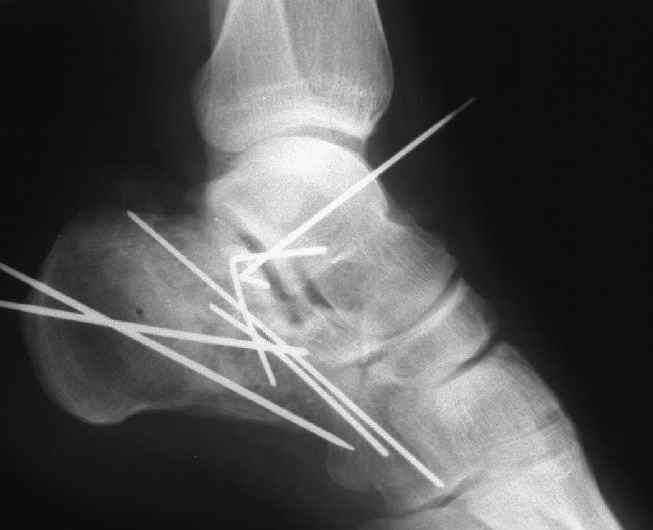

Накладываем спицевой дистрактор, позволяющий выхаживать м/ткани и одновременно устранять захождение отломков.

Окончательная фиксация спицами, пяточными пластинами (5) , в последнее время стали применять крючковидные пластины (ДЕОСТ) (6,6a).